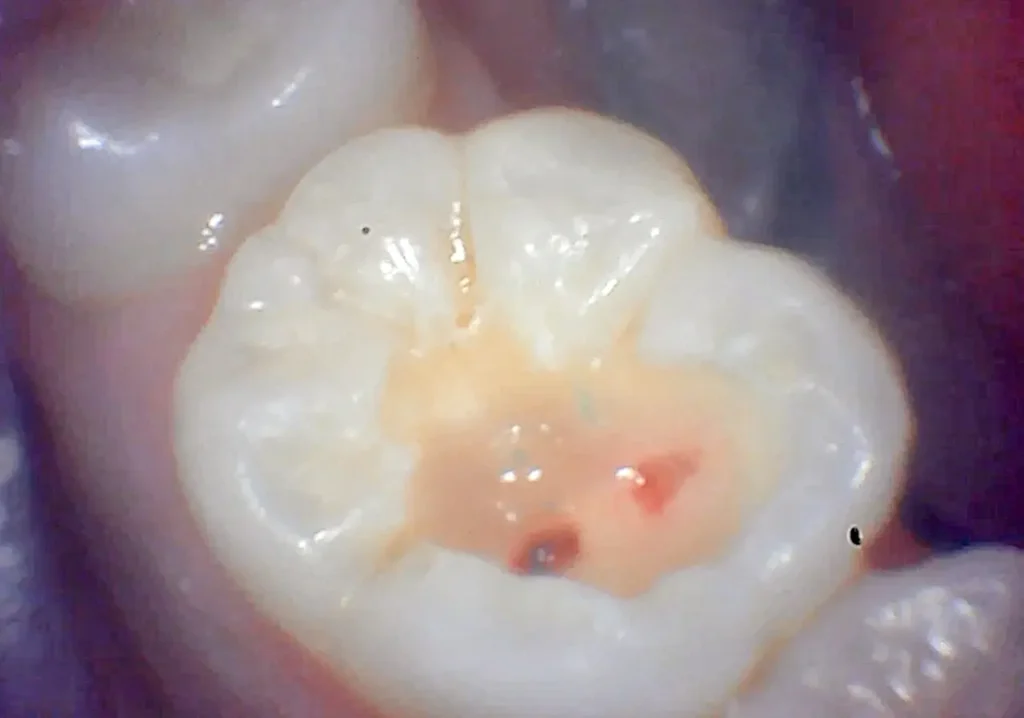

むし歯除去後の写真

悪いところを全て除去した結果、神経が露出していました、根管治療が必要です